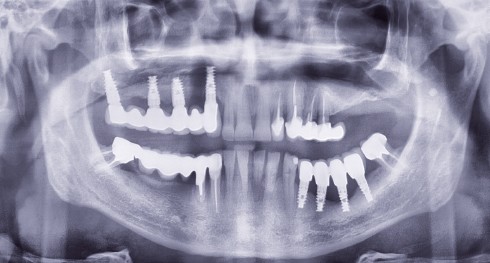

Article réservé à nos abonnés Infraclusie et implant

D’après une étude de Bjork et coll. [1] sur la croissance faciale au maxillaire, il a été établi que la...